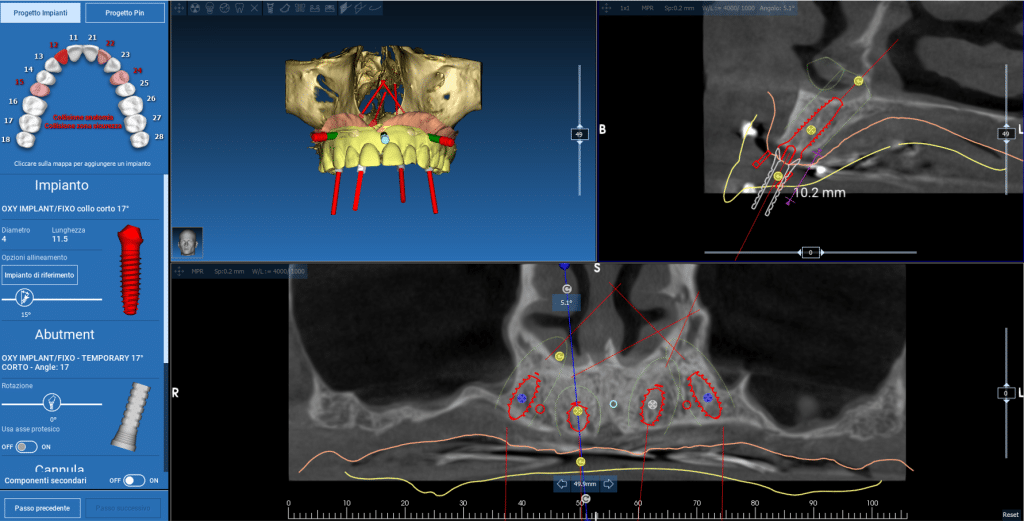

Infatti, in alcuni casi, se le condizioni cliniche lo consentono, posizioniamo (carichiamo) i nuovi denti sugli impianti lo stesso giorno in cui questi vengono inseriti e, talvolta, possiamo fare tutto ciò senza neanche incidere la gengiva grazie alla chirurgia guidata!